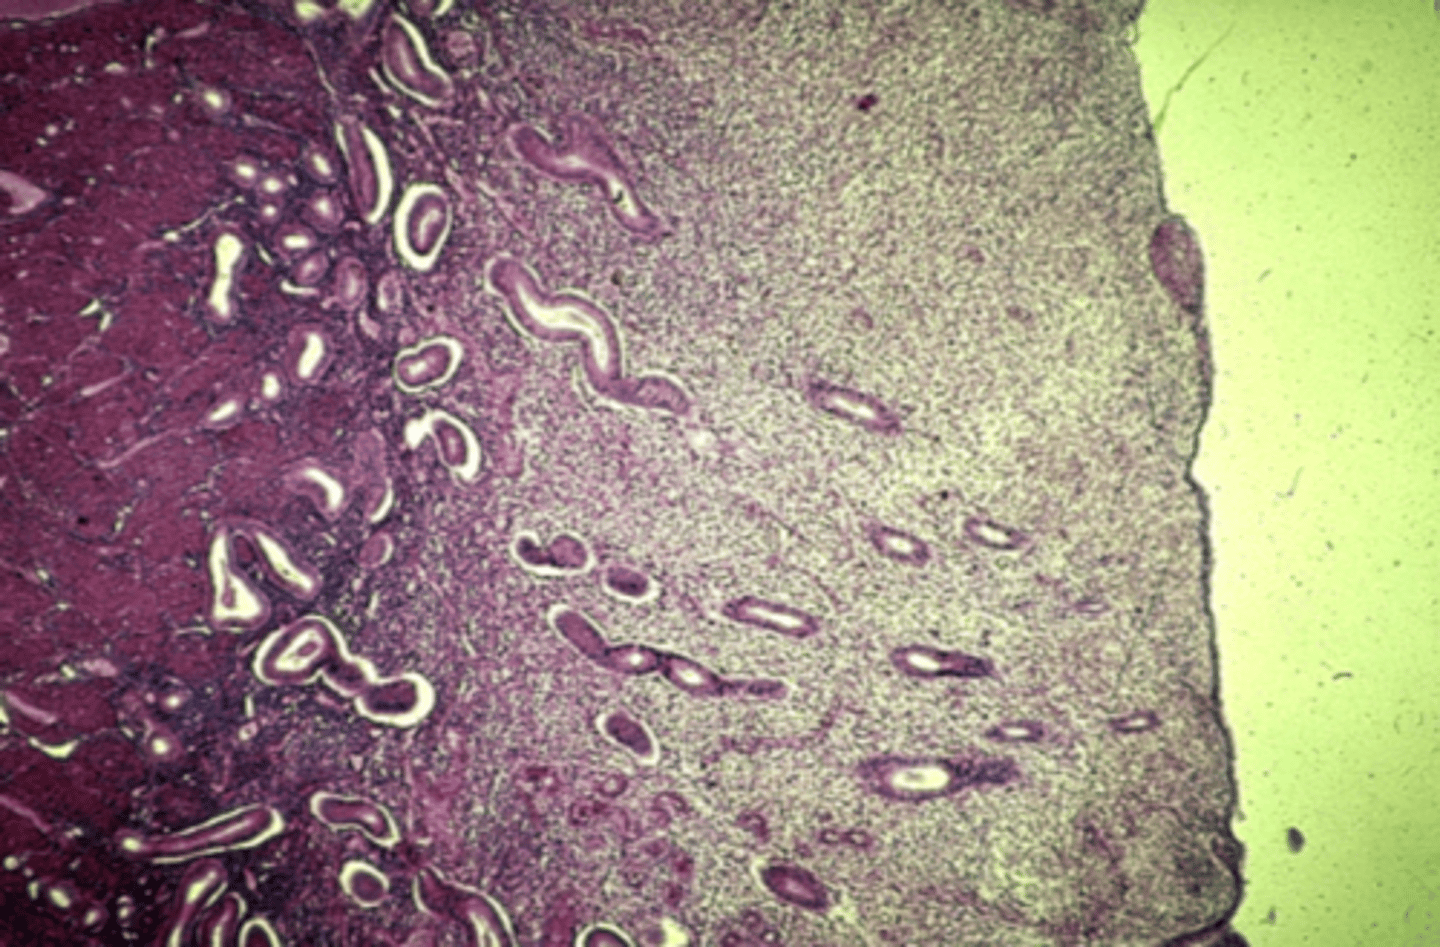

Kidney

What is this?

Glomerulus in kidney

What is this?

ureter

What is this?